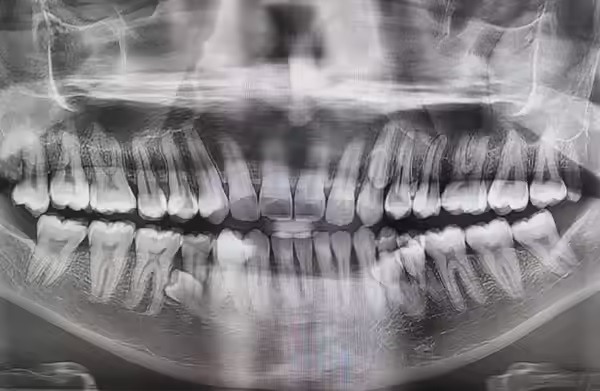

प्रथाब को अपनी इस खासियत का पता बहुत बाद में चला। साल 2021 में जब वह अपने परिवार के साथ बैठकर चाय पी रहे थे तब उन्हें महसूस हुआ कि उनके मसूड़ों में कुछ अतिरिक्त हलचल हो रही है। जब परिवार ने मजाक-मजाक में उनके दांत गिने तो संख्या 38 निकली। इसके बाद जब उन्होंने डेंटिस्ट से संपर्क किया और एक्स-रे कराया तो पता चला कि 4 दांत अभी अंदर छिपे हुए हैं जो बाहर आने की तैयारी में हैं।

धीरे-धीरे वे अतिरिक्त दांत भी बाहर आ गए और साल 2023 की शुरुआत तक प्रथाब के मुंह में दांतों की कुल संख्या 42 हो गई। दिलचस्प बात यह है कि आमतौर पर अतिरिक्त दांत (Hyperdontia) टेढ़े-मेढ़े या दर्दनाक होते हैं लेकिन प्रथाब के मामले में दसों अतिरिक्त दांत लगभग सीधी लाइन में उगे हैं।